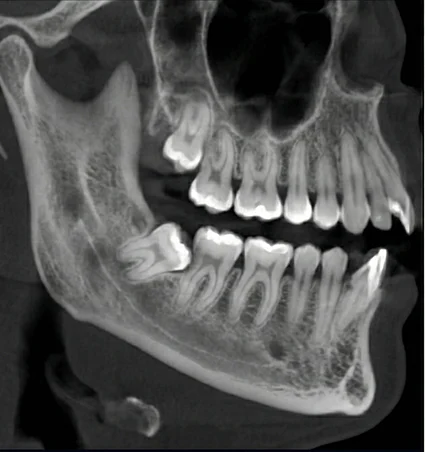

Not every wisdom tooth requires the same type of extraction. Fully erupted wisdom teeth may be removed with a simple extraction using local anesthesia. Teeth that are impacted beneath the gums or bone often require a surgical approach to allow safe removal.

Sedation options such as nitrous oxide, oral sedation, or IV sedation may be used based on comfort needs, with care provided through sedation dentistry when appropriate. Treatment decisions are guided by X-rays, age, oral health, and individual comfort considerations.